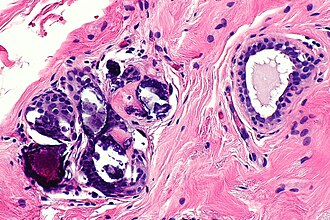

Calcification in benign breast tissue. H&E stain. (WC/Nephron)

• Purple globs (with concentric rings) on H&E - represent calcium phosphate.

• Often in the lumen of a gland, may be in the stroma.

• Calcific material typically has a well-demarcated border +/- "sharp corners".